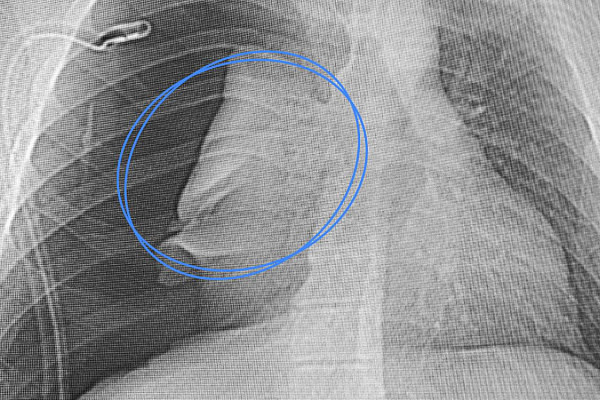

Наши врачи решили не подвергать юного пациента дополнительной хирургической агрессии и обойтись малоинвазивной и абсолютно бескровной методикой. Через естественные дыхательные пути установили эндотрахеальный нитиноловый стент с защитным покрытием. Он перекрыл дефект, лёгкое сразу расправилось и начало выполнять свои функции. Но на восстановление целостности стенки трахеи за счёт рубцовой ткани потребовалось время. Устройство извлекли через три недели, убедившись в успешном результате лечения. Подросток выписан без ограничительных рекомендаций.